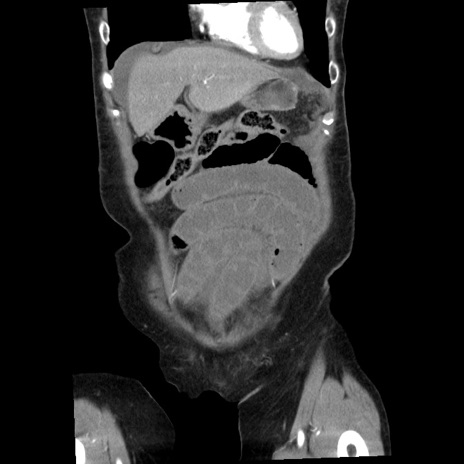

症例1(冠状断像)

【症例】80歳代女性

【主訴】腹痛

【現病歴】8時間前から腹痛あり来院。

【既往歴】糖尿病、脂質異常症、子宮体癌にて子宮全摘術

【身体所見】意識清明・会話良好だが腹痛で苦悶様、全腹部にわたって反跳痛と圧痛あり

【データ】WBC 13600、CRP 0.14、LDH 224、CK 90